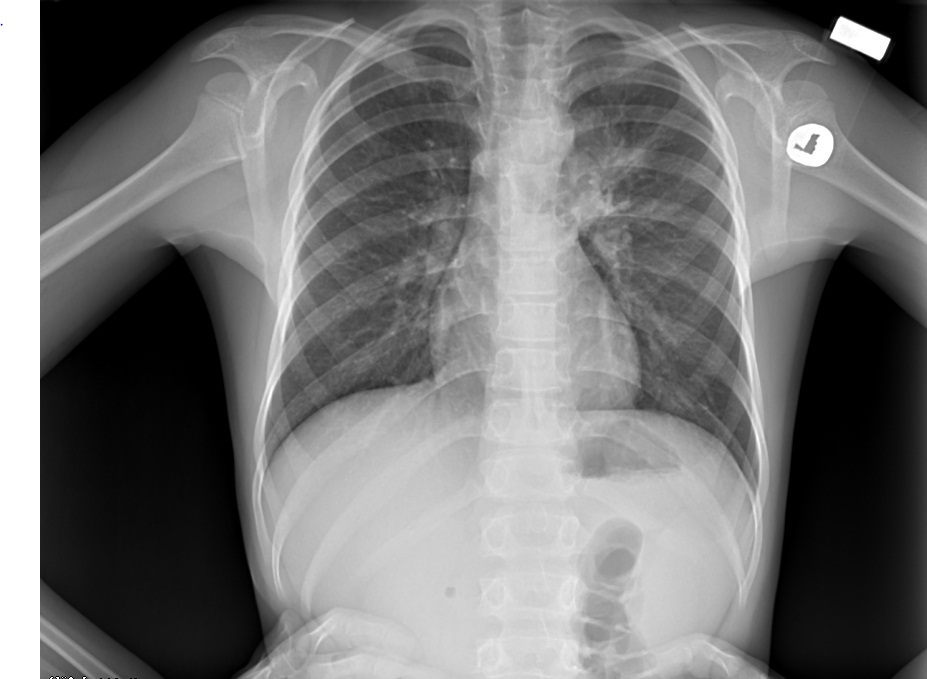

Воспаление Легких На Снимке Рентгена Фото💣 👉🏻👉🏻👉🏻 ИНФОРМАЦИЯ ДОСТУПНА ЗДЕСЬ! КЛИКАЙ 👈🏻👈🏻👈🏻Воспаление Легких На Снимке Рентгена Фото